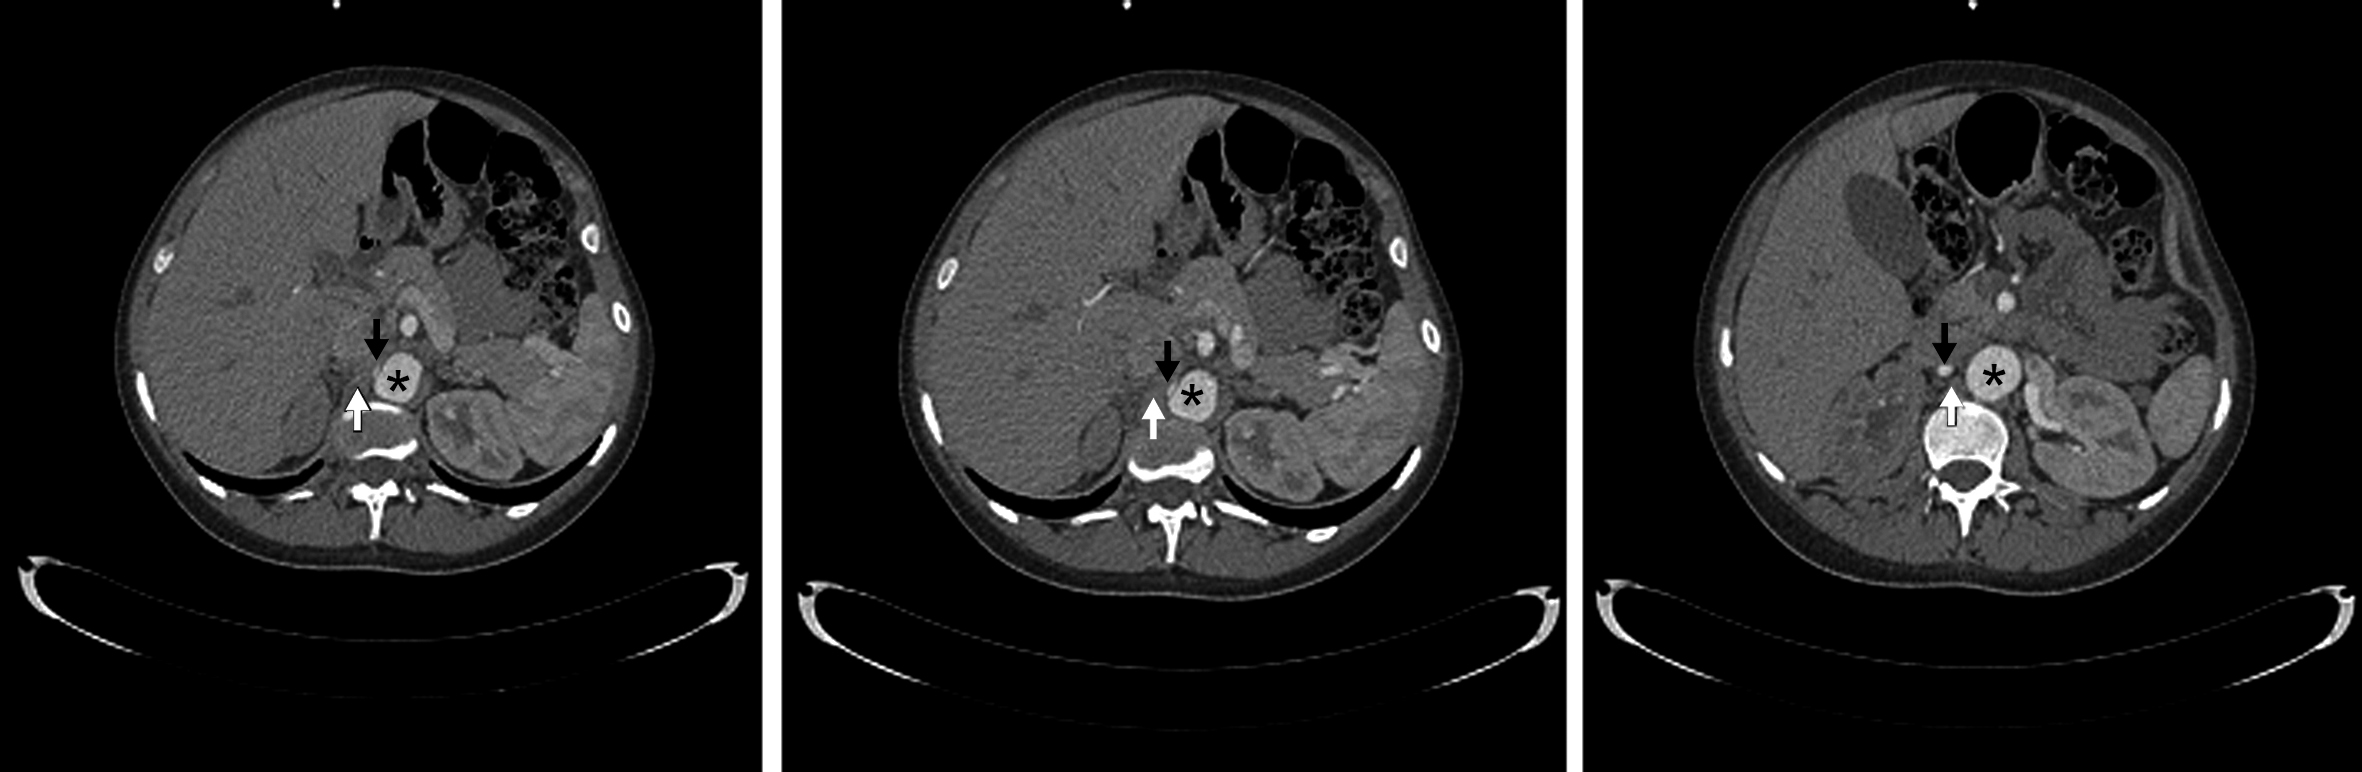

Figura 2

Angiografía de Aorta por TC Proyección de máxima intensidad. Cortes coronales. (*) Aorta abdominal, (flecha blanca) Crura diafragmática derecha, (flecha negra) Arteria renal derecha.

La arteria renal derecha es única, se encuentra permeable, y presenta franca disminución de su calibre y trayecto “verticalizado” en su sector proximal, transcurriendo entre la aorta abdominal y la crura diafragmática ipsilateral en su segmento inicial. Distalmente la arteria renal derecha presenta calibre normal, de aprox. 6 mm de diámetro. Así mismo se observa realce asimétrico de ambos riñones tras la administración de medio de contraste i/v, evidenciándose menor captación del mismo en forma difusa a derecha (nefrograma tardío) en comparación con el riñón contralateral, lo cual traduce hipoperfusión renal. (Figs. 1 y 2)

El tronco celíaco y la arteria mesentérica superior se encuentran permeables y de calibre habitual. Se identifica un origen alto de las ramas viscerales de la aorta abdominal, a saber, el tronco celíaco a la altura del espacio discal T11-T12, la arteria mesentérica superior a nivel del cuerpo vertebral de T12, la arteria renal derecha a nivel del espacio T12-L1 y de la arteria renal izquierda a nivel del margen superior de cuerpo de L1. (Fig. 3)